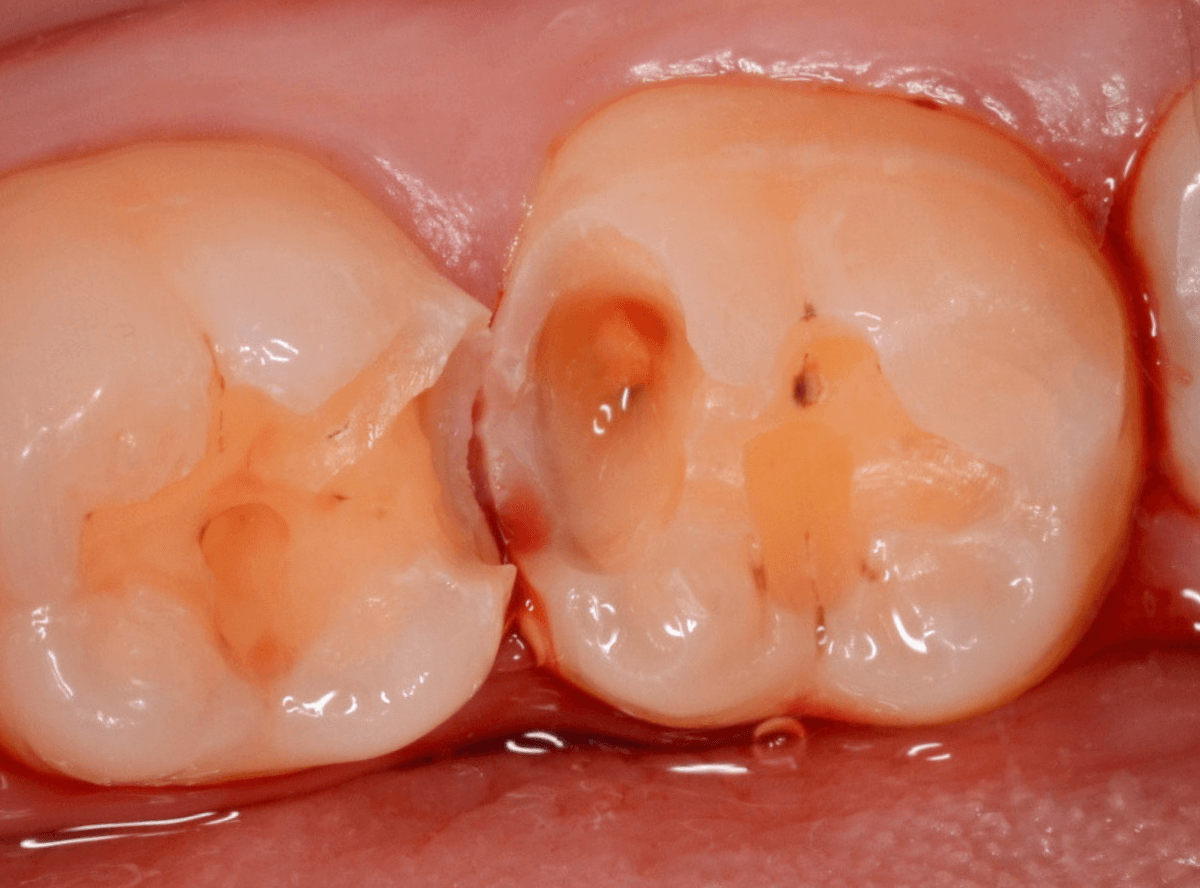

Case.10 レントゲンに写らない側面の虫歯を、少しずつ削って調べる

こちらも、虫歯が歯のあちこちで進行してしまっている患者さんのケースです。

特に側面の虫歯が深そうです。

側面にできた虫歯はレントゲン写真では診断しづらくやっかいです。

今回は「見るからに深そう」ですが。

さすがにレントゲン写真でも虫歯がありそうな事は確認できますが、実際にどうなってるのかはあまりはっきりわかりません。

少しずつ虫歯を除去していきます。

歯の側面から、手前の歯までつながった虫歯になっていました。

手前の歯までの虫歯を除去しました。

歯の後ろ側の側面も、大きな虫歯になっていますので、処置します。

隣の歯との間(隣接面)は、中で虫歯が広く進んでることが多いです。

結局、前後の歯に渡る広い虫歯でした。

レントゲン写真だけでは、ここまでの虫歯は判断できませんでした。